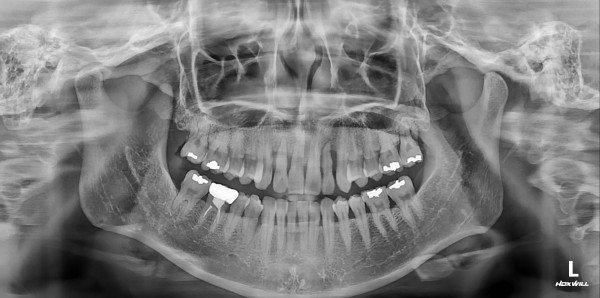

임플란트 센터 | 여) 41세